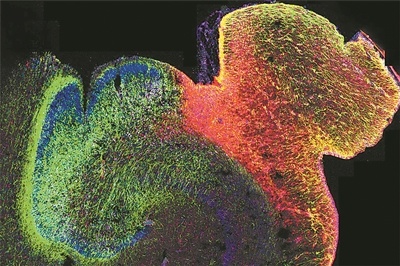

科技日报北京10月9日电 (记者张佳欣)由美国加州大学洛杉矶分校牵头的一项研究,揭示了人类大脑发育过程中基因调控的演变方式,并展示了染色质的3D结构在其中发挥的关键作用。研究人员绘制了海马体和前额叶皮质中DNA修饰的首张图谱,这两个大脑区域对学习、记忆和情绪调节至关重要,也常与自闭症和精神分裂症等疾病相关。这项研究为早期大脑发育如何影响身心健康提供了新的见解。相关研究9日发表在《自然》杂志上。

正在发育的人类海马体的荧光图像。图片来源:美国加州大学旧金山分校

为了绘制该图谱,研究人员采用了一种尖端测序方法,即单核甲基化测序和染色质构象捕获技术,能同时分析控制单个细胞基因表达的两个表观遗传机制。搞清这两个调控机制如何作用于影响发育的基因,是理解这一过程出错而导致神经和精神疾病的关键步骤。

研究人员分析了从中期妊娠到成年期的供体提供的超过53000个脑细胞,揭示了关键发育窗口期间基因调控的重大变化,构建出人类大脑发育关键时间点发生的巨大遗传重组的全面图景。

研究人员表示,婴儿大脑发育最活跃的阶段发生在孕中期左右。被称为放射状胶质细胞的神经干细胞在第一和第二孕期已经产生了数十亿个神经元。这时,它们停止产生神经元并开始产生支持和保护神经元的胶质细胞。同时,新形成的神经元逐渐成熟,获得履行特定功能所需的特征,并形成突触连接以进行通信。

这一发现或有助于识别神经发育和神经精神疾病中有意义的遗传风险因素,对改进大脑类器官等基于干细胞的模型具有重要意义。